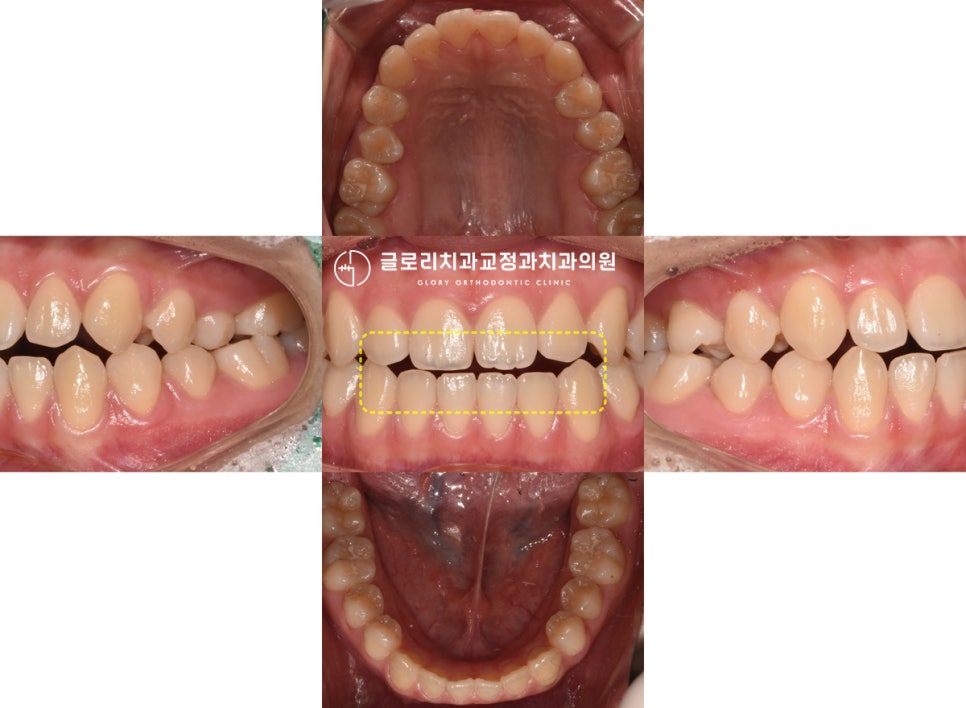

1. 초진

위, 아래 이가 긴밀하게 붙지 않고

떨어져 있는 것을 확인할 수 있었습니다.

표시해둔 곳을 보면 윗니가 아랫니의

1/3 정도 덮고 있어야 되는 게 정상이지만,

아예 붙어 있지 않은 것을 볼 수 있는데요.

다행히 다른 곳은 크게 틀어지거나

삐뚤어진 곳 없이 양호한 편에 속하네요ㅎㅎ

환자께서는 입이 다물어지지 않아

면 음식을 먹기도 불편하고

입이 계속 건조한 느낌이라며 말씀을 해주셨는데요.